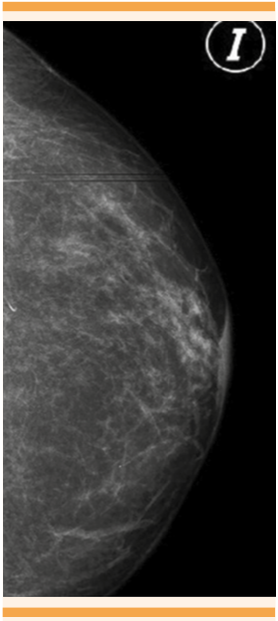

El estudio de inmunohistoquímica reportó positividad para CK7 y HER2, y negatividad para p53 a células neoplásicas, con lo que se estableció el diagnóstico definitivo de enfermedad de Paget mamaria (Figura 3 y 4). Los estudios de mastografía anuales se reportaron normales, excepto el último (Figura 5), que mostró ambas mamas con patrón fibroglandular disperso, aumento del grosor de la piel del complejo areola-pezón, con aplanamiento del pezón, sin evidencia de nódulos en la región retroareolar, correspondiente con calcificaciones benignas bilaterales, clasificación BIRADS 5. El ultrasonido no mostró alteraciones. La paciente fue enviada al servicio de Oncología quirúrgica para su valoración y se realizó la mastectomía total, cuyo reporte final de patología reveló un carcinoma intraductal sin componente invasor. Figura 6

En el caso aquí reportado se solicitó inicialmente la mamografía, pues se considera el estudio radiológico de elección para detectar algún carcinoma invasivo o intraductal in situ, pero con limitaciones en este último. 1,5 La sensibilidad de la mamografía para la detección de neoplasias mamarias con y sin masa palpable es de 97 y 50%, respectivamente. 2 Una revisión de casos de enfermedad de Paget mamaria e imágenes radiológicas describió los siguientes hallazgos: 6 engrosamiento de la piel, específicamente en la región areola-pezón, densidad asimétrica, retracción del pezón y una masa discreta, ya sea subareolar o distante de la zona areola-pezón. Otros hallazgos incluyen: calcificaciones pleomórficas malignas, asociadas o no con engrosamiento o distorsión de la anatomía mamaria.